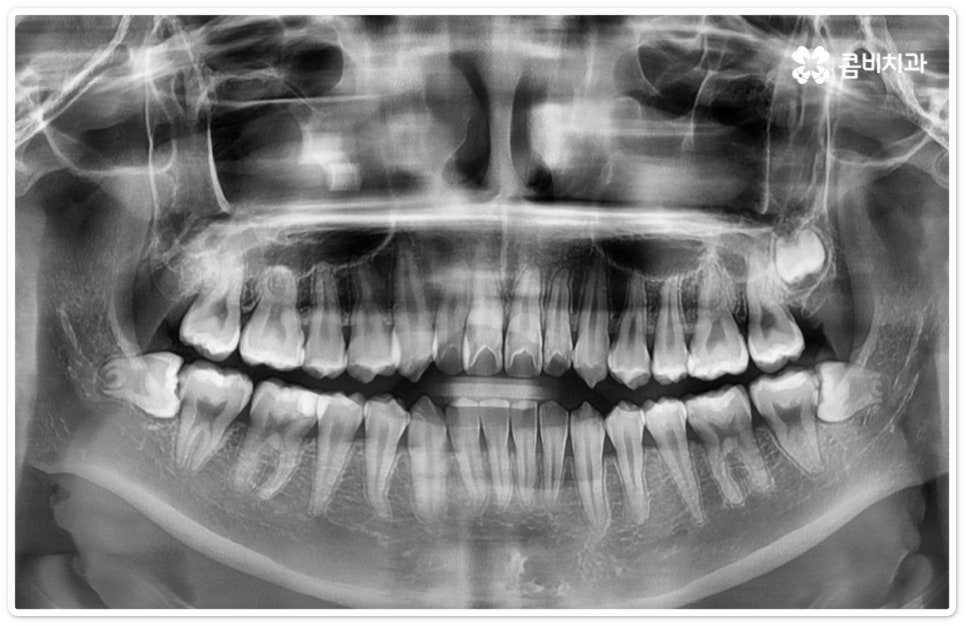

사랑니의 개수, 위치, 각도나 뿌리의 형태, 매복 깊이 등은 사람마다 다른데 그 중에서 특히 완전히 매복된 상태로 비스듬히 누운 채 자리잡은 아래 사랑니의 경우 턱을 가로지르는 하치조 신경과 가깝기 때문에 누운사랑니발치 시 신중을 기하지 않으면 혹시 모를 부작용인 감각 이상을 초래할 수 있으므로 뛰어난 해부학적 지식과 풍부한 임상 경험, 세심한 기술력을 가지고 있는 숙련된 의료진에게 치료를 받으시길 권유드리고 있어요. 혹시라도 신경 손상이 발생하게 되면 입술이나 턱이 마취된 듯 침이 흘러도 감각이 없거나 양치질을 할 때 물이 입술밖으로 세어나가는 상태가 유발될 수 있으니 조심해야 할 거예요.

매복 형태의 사랑니는 잇몸을 절개하고 발치해야 하며, 특히 깊숙하게 누운사랑니발치 시에는 신경을 건드리지 않도록 사랑니를 조각내어 조심해서 빼내야 할 뿐 아니라 환자분들의 상태에 따라 잇몸뼈를 조금씩 삭제해야 할 수도 있기 때문에 이러한 고난도 시술에는 주변 조직의 손상을 최소화하고 혹시 모를 부작용의 위험을 줄이며 출혈 및 통증이 커지지 않도록 하기 위해서 시술자의 높은 숙련도가 더욱 요구된다고 할 수 있어요. 또한 매복된 사랑니의 각도, 뿌리 형태, 인접 치아와의 관계, 신경 위치 등을 정확하게 파악하고 체계적인 맞춤 계획을 세워 무리하지 않게 사랑니 발치 수술을 진행하기 위해서 정밀 진단이 가능한 3D CT 장비가 있는 치과에서 꼼꼼한 검사부터 받아보는 것이 중요할 거예요.